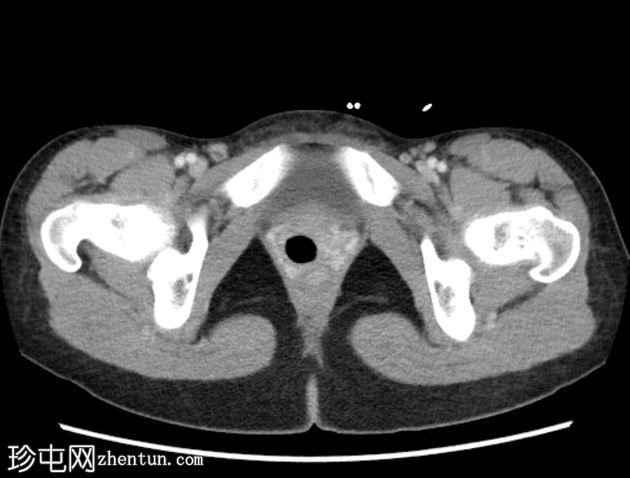

轴位增强扫描(门静脉期)

2.jpeg

定位片、轴位、矢状位及冠状位图像均可见阴道内有一根线状充气棉塞。棉塞的线头在本例中清晰可见。

阴道内有一根棉塞(女性卫生用品),是月经期女性在X线检查中常见的偶然发现。它们由棉和人造丝制成,容易滞留空气,因此在影像检查中,它们会呈现出阴道的形状和方向。有时,也能看到卫生棉条的线,就像本例中一样。放射科医生应该能够识别阴道卫生棉条,以免将其与病变混淆。